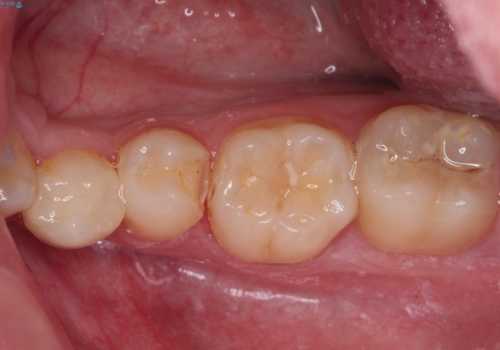

詰め物が欠けた セラミックインレーによる修復

- 以前治療した詰め物が欠けてしまったことを主訴として来院した患者様です。

食べ物がはさまったり、冷たいものがしみるといった症状がみられました。

むし歯の染め出し液と拡大鏡を用いて、むし歯がないことを確認し、

セラミックインレーにて修復することとしました。